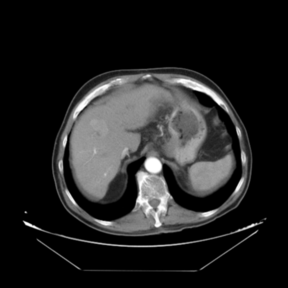

In addition to the previous measurements, the visual outcomes of two of the experiments are shown in [[#img-3|Figures 3]] and [[#img-4|4]], whose purpose is to highlight the most illustrative differences (from a medical point of view) between the results provided by the compared methods. In  [[#img-3|Figure 3]], we observe a normal size of the liver, with discretely irregular contours and homogeneous signal intensity. In hepatic segment II, there is a lesion of 40 mm of maximum axis, encapsulated and with well-defined contours and heterogeneous enhancement in arterial phase (after administration of intravenous contrast), suggestive of hepatocellular carcinoma (HCC). In this slice of the CT scan, we can also observe the aorta that shines in the arterial phase, the lower area of the stomach and the upper area of the spleen. In  [[#img-4|Figure 4]], the liver has a normal size with discretely irregular contours in relation to changes due to chronic liver disease. In hepatic segment IV, a 36 mm diameter focal lesion is identified, which has arterial phase enhancement with a small area of necrosis of 13 mm; it corresponds to a HCC previously chemoembolized with partial necrosis. In this slice of CT, we can also observe the aorta, the gastric chamber and the spleen. When comparing the two methods under study, it can be seen how in  [[#img-3|Figure 3]] the resulting registered datasets are very similar. However, looking closely, it can be noticed that in the right part of the image (left side of the patient) the shape and width of the structures corresponding to the stomach and the spleen in  [[#img-3|Figure 3]](d) match better those in the reference dataset. Likewise, the part of the rib at the upper right of the image is more similar to the same region in the reference dataset by using the proposed method. Regarding the experiment shown in  [[#img-4|Figure 4]], it can be easily appreciated how the geometrical matching (with respect to the reference dataset,  [[#img-4|Figure 4]](a)) of the structures in the right side of the image (specially the gastric chamber) is visually more satisfactory in  [[#img-4|Figure 4]](d). Moreover, the area of tumor necrosis which results from the proposed method is also slightly better aligned.

In addition to the previous measurements, the visual outcomes of two of the experiments are shown in figures Fig.[[#img-3|3]] and Fig.[[#img-4|4]], whose purpose is to highlight the most illustrative differences (from a medical point of view) between the results provided by the compared methods. In Fig.[[#img-3|3]], we observe a normal size of the liver, with discretely irregular contours and homogeneous signal intensity. In hepatic segment II, there is a lesion of 40 mm of maximum axis, encapsulated and with well-defined contours and heterogeneous enhancement in arterial phase (after administration of intravenous contrast), suggestive of hepatocellular carcinoma (HCC). In this slice of the CT scan, we can also observe the aorta that shines in the arterial phase, the lower area of the stomach and the upper area of the spleen. In Fig.[[#img-4|4]], the liver has a normal size with discretely irregular contours in relation to changes due to chronic liver disease. In hepatic segment IV, a 36 mm diameter focal lesion is identified, which has arterial phase enhancement with a small area of necrosis of 13 mm; it corresponds to a HCC previously chemoembolized with partial necrosis. In this slice of CT, we can also observe the aorta, the gastric chamber and the spleen. When comparing the two methods under study, it can be seen how in Fig.[[#img-3|3]] the resulting registered datasets are very similar. However, looking closely, it can be noticed that in the right part of the image (left side of the patient) the shape and width of the structures corresponding to the stomach and the spleen in Fig.[[#img-3|3]](d) match better those in the reference dataset. Likewise, the part of the rib at the upper right of the image is more similar to the same region in the reference dataset by using the proposed method. Regarding the experiment shown in Fig.[[#img-4|4]], it can be easily appreciated how the geometrical matching (with respect to the reference dataset, Fig.[[#img-4|4]](a)) of the structures in the right side of the image (specially the gastric chamber) is visually more satisfactory in Fig.[[#img-4|4]](d). Moreover, the area of tumor necrosis which results from the proposed method is also slightly better aligned.